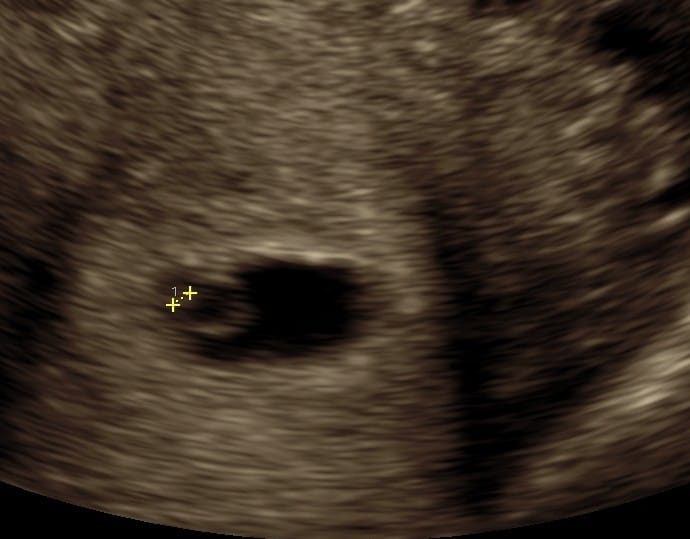

Praksisjordemoders tidlige tryghedsscanning (uger 5+0‑7+0) giver dig muligheden for:

- at bekræfte graviditet i livmoderen,

- at se hjerteblink, fra 6+3

- at få en foreløbig terminsberegning og stille spørgsmål til jordemoderen.